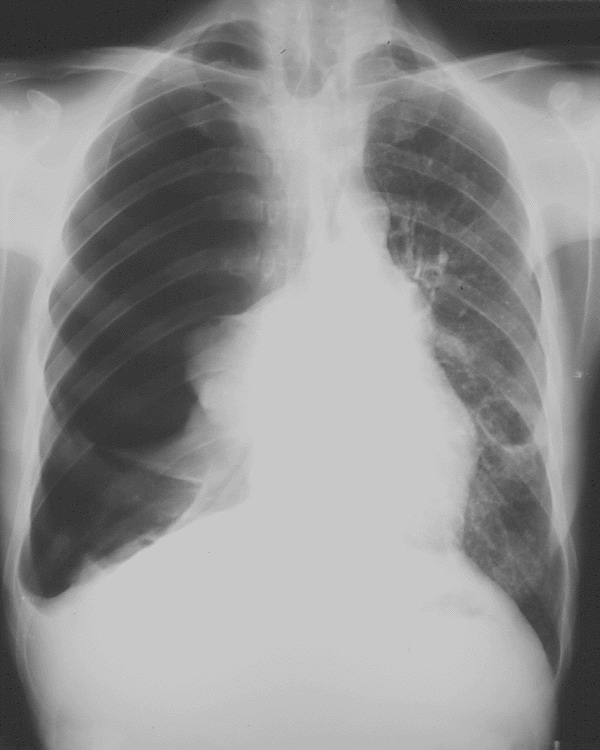

El último tipo de estado de shock de conoce como

obstructivo. Este se debe a diversas afecciones como un neumotórax a tensión,

una embolia pulmonar, un tumor que obstruya e imposibilite la correcta función

cardiaca o un taponamiento cardiaco.

| Tomado de http://aceue.blogspot.mx/2009/11/neumotorax.html |